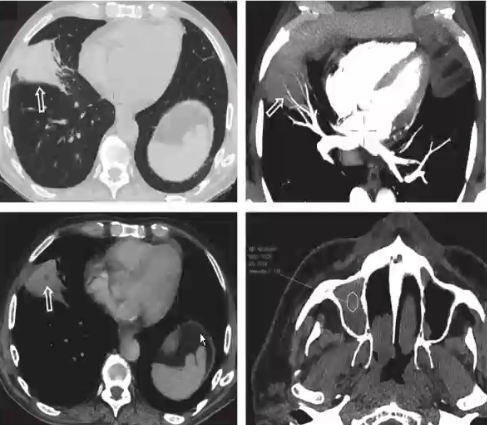

❖ 侵袭性镰刀菌肺炎一般表现为小气道或者支气管周围浸润影,其次为大结节样实变伴低密度征

❖ 晕征和血管阻塞征少见

❖ 肺部浸润影伴低密度征,但无晕征和血管阻塞需考虑镰刀菌肺炎,特别是合并高密度上颌窦和筛窦炎者